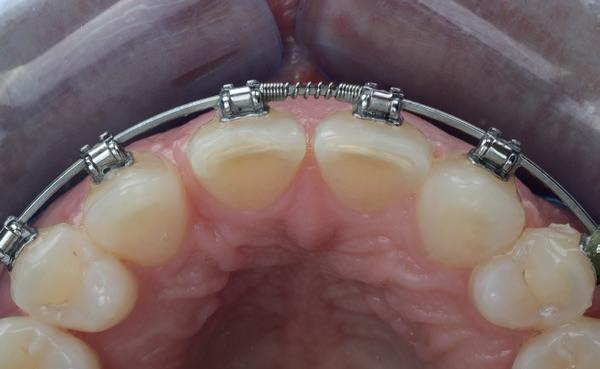

Een 47-jarige vrouw wordt aan het einde van het orthodontische traject door haar eigen tandarts naar mij verwezen voor een intake en eventuele behandeling. Bij mevrouw zijn elementen 12 en 22 afwezig. De 13 en 23 zijn gemesialiseerd. Haar eigen tandarts vraagt of ik het front met composiet kan restaureren om weer een harmonieuze glimlach te krijgen (Afbeelding 1).

Tijdens de intake wordt een complete lichtfoto status gemaakt om de positie van de elementen goed in kaart te brengen en een behandelplan op te kunnen stellen. Op de close-up foto van het bovenfront (afbeelding 2) zien we dat er sprake is van slijtage aan element 11. Elementen 12 en 22 zijn afwezig en elementen 13 en 23 zijn gemesialiseerd. Tussen element 11 en 13 is er sprake van een diasteem. Dit diasteem is niet aanwezig aan de andere zijde (afbeelding 3).

Dit zorgt voor een lastige situatie, omdat bij het sluiten van dit diasteem (dit is de wens van de patiënt) elementen 13 en 11 breder zullen worden dan elementen 21 en 23. Dit is één van de redenen waarom ik patiënten altijd graag aan het einde van het orthodontist traject wil zien. Op dat moment is het nog mogelijk om kleine wijzigingen door te voeren, voordat de beugel definitief wordt verwijderd. Na de intake stuur ik een terugrapportage naar de orthodontist waarbij ik vraag om de elementen zo te positioneren dat de ruimte beter verdeeld is.

Ik zie mevrouw een aantal weken later terug voor evaluatie (afbeelding 4). Er is een klein centraal diasteem ontstaan en daardoor is het diasteem tussen de 11 en 13 ook kleiner geworden. Tussen de 21 en 23 is geen diasteem aanwezig (afbeelding 5), waardoor er hoogstwaarschijnlijk wel iets breedte verschil zal zijn tussen de linker- en rechterzijde.

Met composiet wordt een snelle mock-up gemaakt om te beoordelen of ik in deze situatie goed kan uitkomen met de ruimte, of dat we wellicht de elementen nog meer moeten verplaatsen (afbeelding 6). Mevrouw is zeer tevreden met de snelle mock-up en daarom wordt besloten dat de orthodontische behandeling afgerond kan worden. Eventuele verschillen in breedte kunnen we proberen optisch zoveel mogelijk te maskeren.

Nadat de vaste apparatuur verwijderd is (afbeelding 7 en 8), zie ik mevrouw voor het maken van een afdruk/scan ten behoeve van een wax-up. Aangezien ik in deze casus wil werken met de injectietechniek, is een wax-up noodzakelijk.

1: Glimlach foto om de positie van de elementen ten opzichte van de lippen te beoordelen.

2: Close-up foto van de voortanden in de bovenkaak.

3: Occlusale foto om de positie van de elementen en de diastemen te beoordelen.

4: Situatie na orthodontische aanpassingen.

5: Occlusale foto om de nieuwe positie van de elementen te beoordelen.

6: Snelle mock-up met composiet om te bepalen of de huidige stand van de elementen de ruimte biedt om de elementen in de juiste vorm op te bouwen.

7: Glimlach foto na verwijderen van de vaste apparatuur.

8: Close-up foto van voortanden na verwijderen vaste apparatuur.